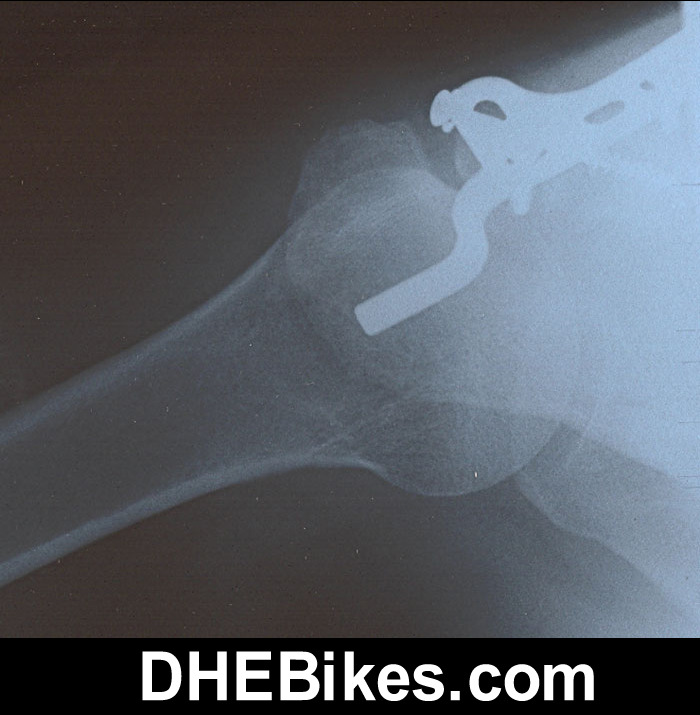

Dave busted up... after a front tire failure off a concrete

staircase jump. Check out the broken clavicle below... and

his post-op x-rays with titanium rods/ bolts. Check out

the titanium in his leg at the bottom of this page :) Have

Click

on the x-ray images below for the larger photo of

DH Dave's right shoulder :)))

X-ray

before the operation...